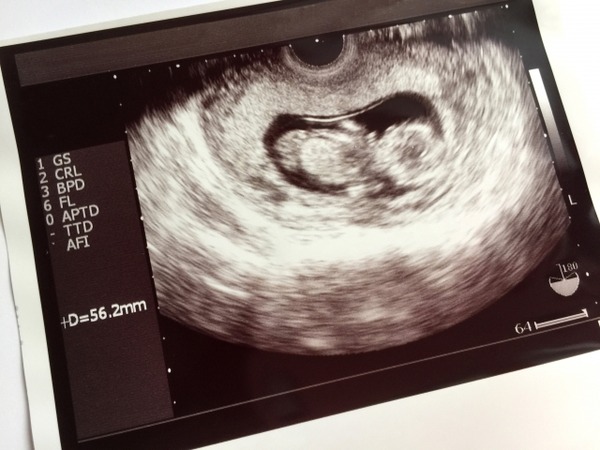

【悲報】嫁ちゃん(38)、「ダウン症を妊娠したみたい…」結果・・・。 歴史 X Facebook はてブ Pocket LINE コピー 2022.03.26 http://blog.livedoor.jp/worldfusigi/js/sp_middle_ad.js 1: 風吹けば名無し 2020/12/01(火) 14:27:43.70 ID:vudapw3/M ワイは堕ろせって言ってるが嫁ちゃんは誤診で正常かもしれなから産みたいだとさ 続きを読む Source: 不思議.NET